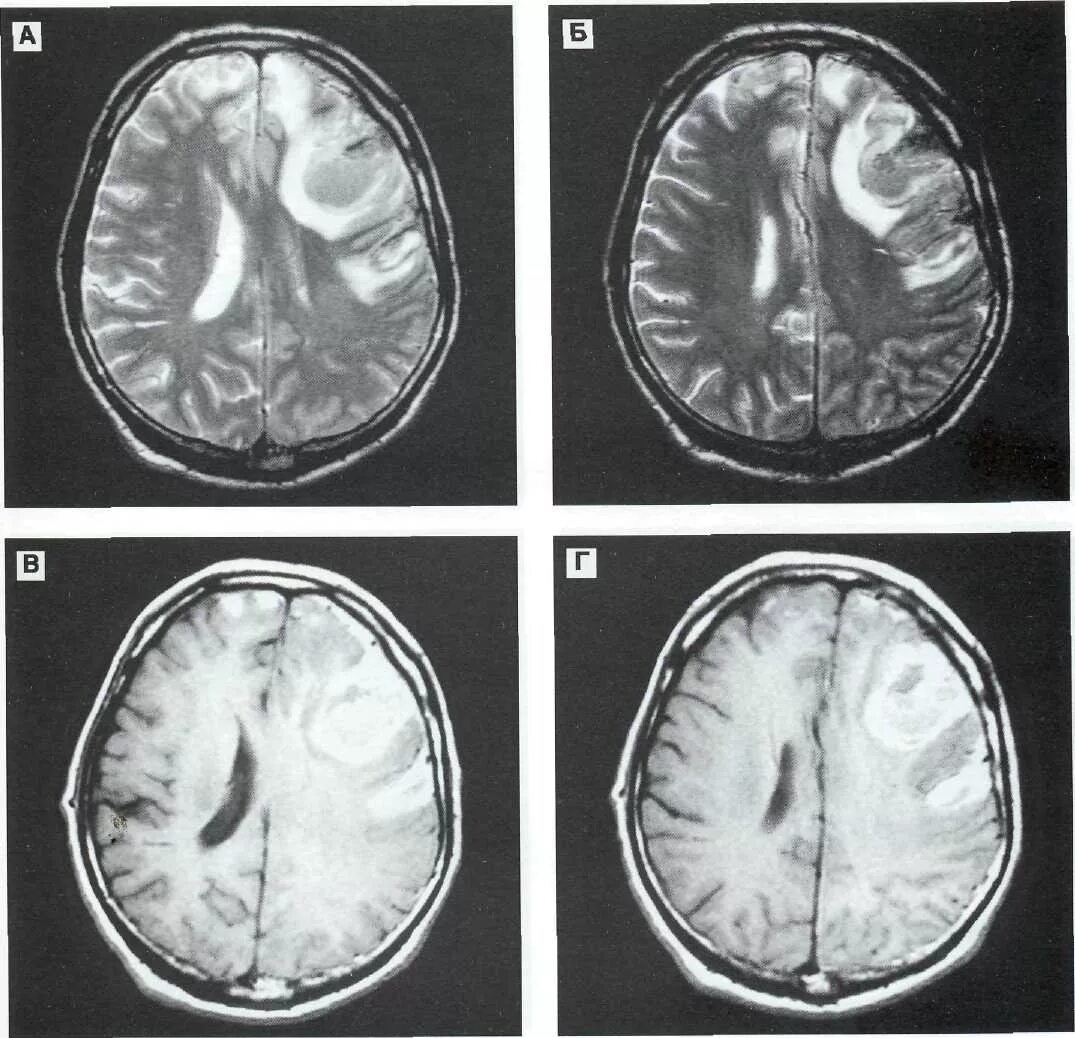

Гематома лобной